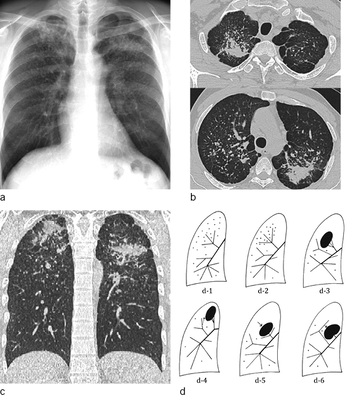

Mikronoduläre Verdichtungen (P-Schatten), mit geringer Streuung sind in den CT-Rekonstruktionen mit 1 mm Schichtdicke schwer von orthogonal getroffenen Gefäßen zu unterscheiden. Auch ein Lungenemphysem kann die Detektion gering gestreuter kleiner silikotischer Knötchen deutlich erschweren. Aus diesem Grund ist die Anfertigung von MIP-(Maximum Intensity Projection)-Rekonstruktionen mit 5-mm-Schichtdicke bei der Diagnostik nodulärer Erkrankungen obligatorisch um den Streuungsgrad sicher einschätzen zu können. Die Schichtdicke von 5 mm wurde gewählt, da die verfügbaren Referenzfilme zum großen Teil ebenfalls mit einer Schichtdicke von 5 mm dokumentiert wurden (  Abb. 4a–d ).